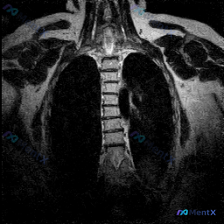

整理到一份胸部冠状位MRI T1加权像的读片资料,先把影像描述放出来,大家来找找核心问题是什么:

- 双侧胸壁肌肉信号基本对称,皮下脂肪清晰;

- 纵隔气管、主动脉弓走行基本正常,未见纵隔肿块;

- 双肺野呈均匀低信号(MRI肺内含气的正常表现);

- 各椎体形态基本完整,骨髓信号均匀(T1加权像下的正常骨髓表现);

- 但胸椎序列在冠状位上未呈直线排列。

📋答案:影像可见明确的胸椎序列侧向弯曲,首要发现为结构性脊柱畸形(脊柱侧弯)。需结合全脊柱站立位X线片测定Cobb角以确诊并分级,同时结合年龄、病史进一步排查特发性、退行性、先天性或神经肌肉源性等病因。